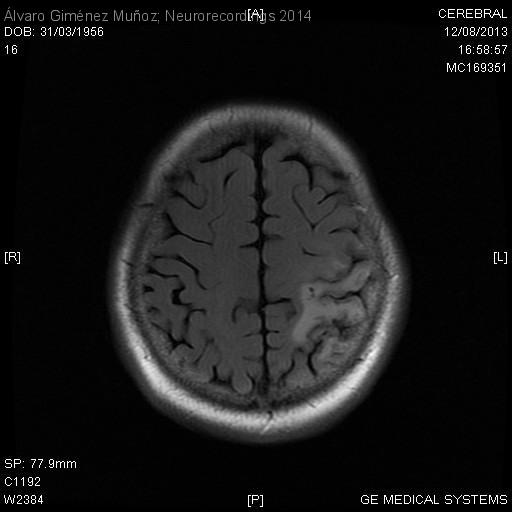

Diagnóstico final: Infarto venoso parietal izquierdo secundario a trombosis de senos lateral y sigmoide izquierdos. Déficit de proteína C.

Neurología: Patología cerebrovascular

Etiología: Ictus

Paciente con antecedentes de tabaquismo, hipertensión arterial, estenosis carotídea derecha asintomática e isquemia crónica de extremidades inferiores. Ingresa en nuestro servicio por un cuadro de debilidad progresiva de extremidad superior derecha de 3 meses de...